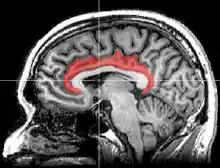

The cingulate cortex is a part of the brain situated in the medial aspect of the cerebral cortex. The cingulate cortex includes the entire cingulate gyrus, which lies immediately above the corpus callosum, and the continuation of this in the cingulate sulcus. The cingulate cortex is usually considered part of the limbic lobe.

![]() Medial surface of left cerebral hemisphere, with cingulate gyrus and cingulate sulcus highlighted. | |